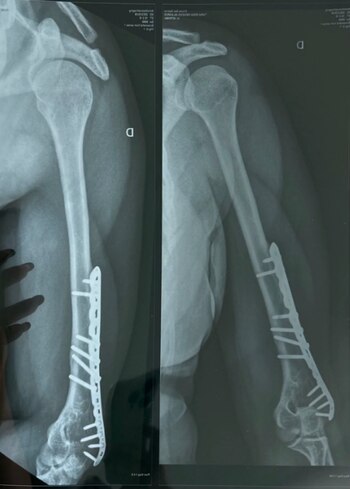

“Como ustedes recordaran, en el año 2014 yo tuve un accidente en las instalaciones de Latina, en donde yo caí varios metros de altura y me rompí el brazo en dos. La fractura afectó uno de los nervios, por ende, en mi primer diagnóstico yo perdí el 95 % de la movilidad de mi brazo derecho. Tuve que pasar por muchas terapias”, dijo en un primer momento.

“Luego que finalizó mi relación laboral con Latina, ellos ya no se hicieron cargo de mí. Yo todavía tengo los clavos, las placas y mi brazo quedó completamente desfigurado. Yo tenía un contrato por locación de servicio con Latina, lo que implica que el empleado es autónomo, no sigue una subordinación”, indicó.